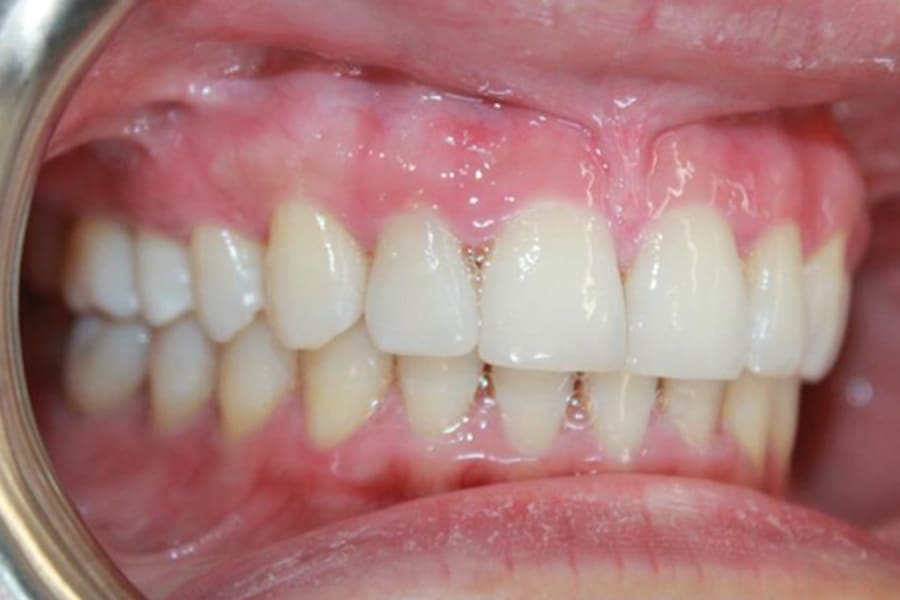

A 35-year-old woman presented with concerns of crowding, bruxism, and bite misalignment, which were associated with a class II malocclusion that would require a combination treatment of expansion, distalization, and molar derotation. ClearCorrect® aligner therapy (Straumann, clearcorrect.com) was selected as the primary modality, as the patient requested a non-invasive, esthetic treatment. The treatment plan was designed to be completed within 6 months of active aligner therapy. Class II elastics were prescribed, and the ClearCorrect FLEX case plan was chosen to allow for refinements, as needed. After comprehensive digital records were taken, the first set of aligners was delivered, engagers were bonded, and the patient was instructed to wear aligners on a 14-day cycle with full-time class II elastic wear. To enhance efficiency, more engagers were placed, including posterior attachments, to maximize control over molar distalization and anchorage. Interproximal reduction of 0.3 mm was performed in a few contacts at the initial appointment to facilitate space closure and alignment. Due to the complexity of the correction and the patient’s history of bruxism, a lower 3-3 bonded retainer was placed, and retainers were fabricated for both arches. The patient expressed a high level of satisfaction with the ClearCorrect aligner therapy, noting the comfort and esthetics of the aligners and the ability to achieve a fully corrected class II occlusion in just 6 months of treatment.